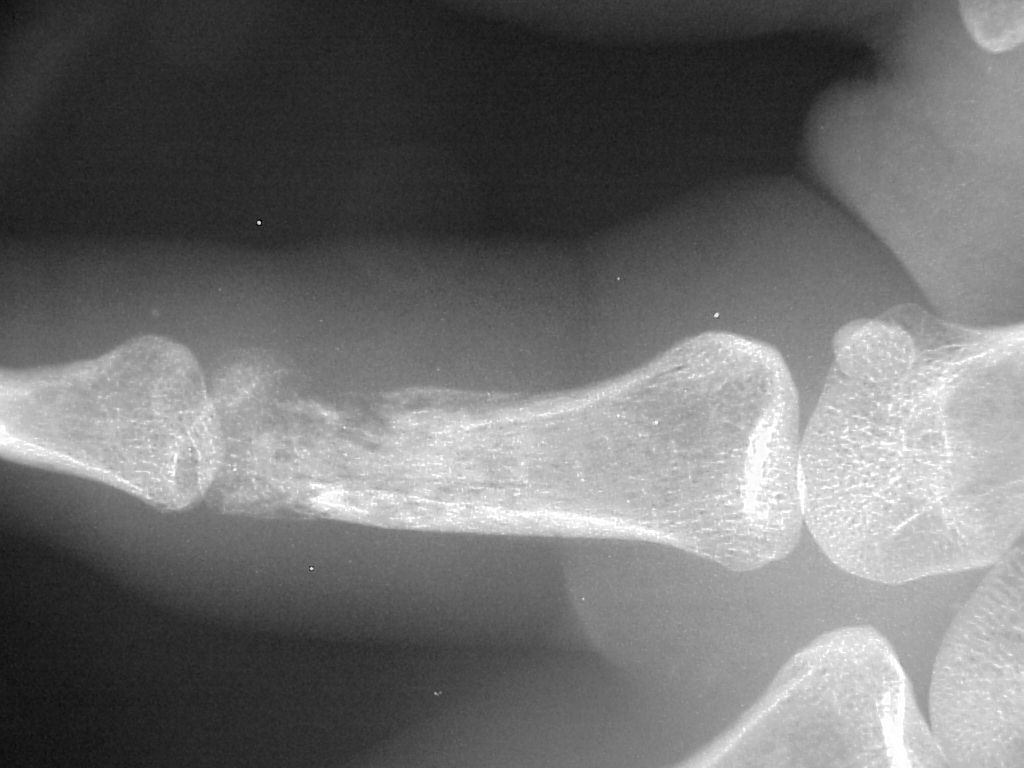

Radiographic erosive changes of the proximal phalanx.